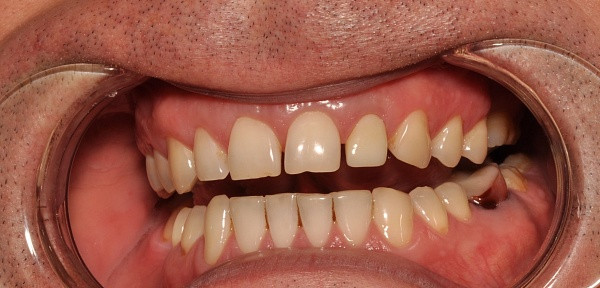

Пациентка, 49 лет. Жалобы частичное отсутствие зубов. Проведено, лечение, удаление несостоятельных зубов, установлены импланты, протезирование коронками из диоксида циркония.